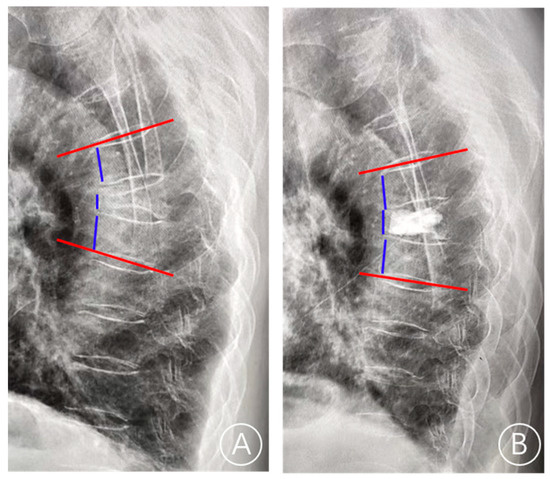

The X-ray film showed a rupture of the anterior cortex of the vertebral body and anterior displacement of bone cement (Figure 1). CT showed a rupture of the anterior cortex of the vertebral body, the anterior edge of the bone cement was more than 2 mm from the anterior edge of the vertebral body, and the bone cement moved forward. MRI examination showed vertebral collapse, and sagittal T1-weighted images and T2-weighted images of the fracture cavity showed abnormally low and high signal intensity, respectively [12]. A typical case is shown in Figure 2.

A plain radiograph showed whether the bone cement is displaced. (A) Bone cement displacement. (B) Non-bone cement displacement.

Figure 3.

The lateral radiograph showed the measurement of the anterior vertebral height and the local Cobb angle. (A) On the preoperative lateral radiographs, the anterior height of the fractured vertebra, the upper adjacent vertebral anterior height, the lower adjacent vertebral anterior height, and the Cobb angle were measured. (B) On the postoperative lateral radiographs, the anterior height of the fractured vertebra, the upper adjacent vertebral anterior height, the lower adjacent vertebral anterior height, and the Cobb angle were measured. The red line is the endplate and the blue line is the anterior vertebral height.